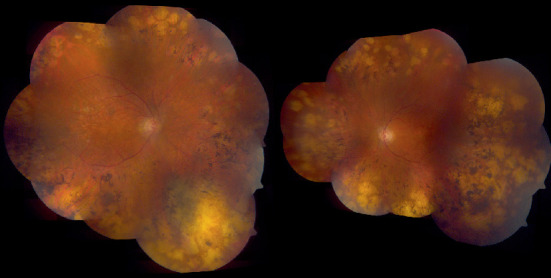

Abstract Image